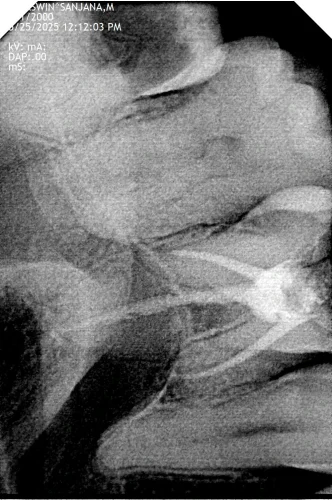

Pulpitis had been diagnosed to be irreversible with an infection of nerve tissue within tooth number 11. Root canal was prescribed in order to remove the infection and save the tooth. Dr. Ashwin utilized an orthograde procedure, which was non-surgical and helped to clean and shape the root canals with the aid of a thorough 3D imaging. The restoration was to be fabricated with the zirconia crown that is strong in nature and provides the natural biting power. The plan was resourceful in patient comfort and clinical efficiency and cost-effectiveness.

Topical and local anesthesia was done. Tooth number 11 was isolated using a rubber dam and kept sterile. Under the guidance of 3D imaging, Dr. Ashwin excised infected tissues with rotary tools and irrigation with a lot of care. The gutted canals were stuffed with gutta-percha and capped with cement. Proper management of pain secured comfort for the patient. Lastly, the zirconia crown, which was very strong and appealing to the eye, was cemented, and this restored the functionality of the teeth.